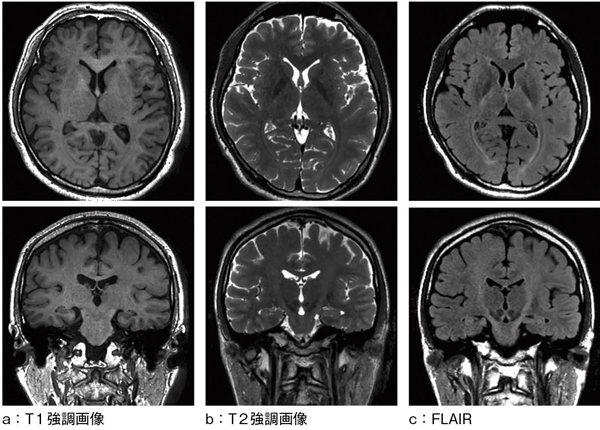

当社の3D FSEシーケンス,isoFSEは,T1強調のほか,T2強調,FLAIR等にも対応(図7),さらには,プロトン密度強調画像やSTIRの取得も可能であり,撮像部位ごとに最適化できる独自の可変refocus flip angle designにより,さまざまな画像コントラストに幅広く対応している。isoFSEが臨床の場で活用されることを強く期待している。そして,将来的には,さらなる高速化技術等によって,MRI検査の時間短縮に大きく寄与できると考えている。

図7 isoFSE reformat image